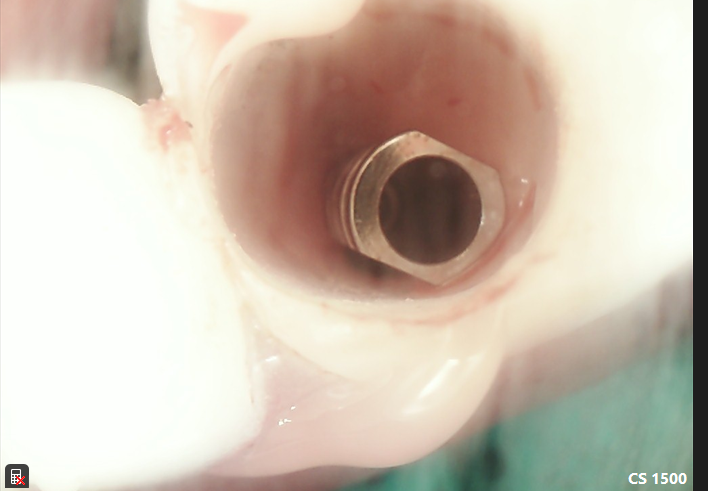

Maxillary AOX W’ Immediate Conversion